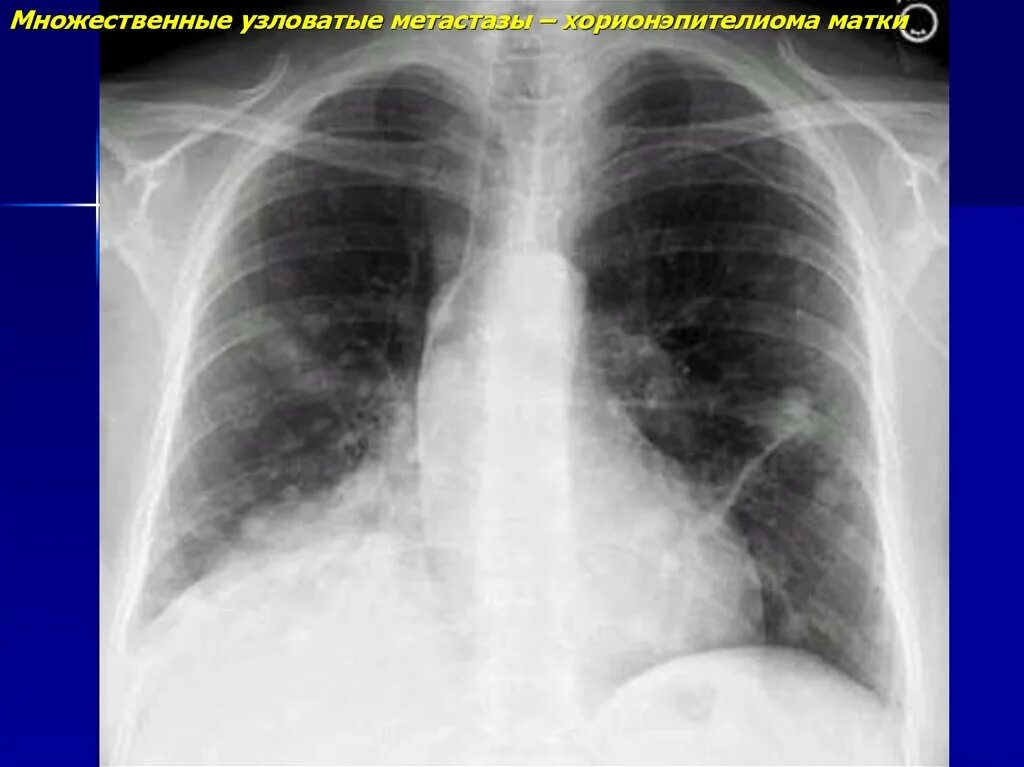

Метастазы бывают доброкачественными